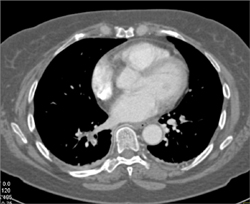

Clot in Aortic Arch